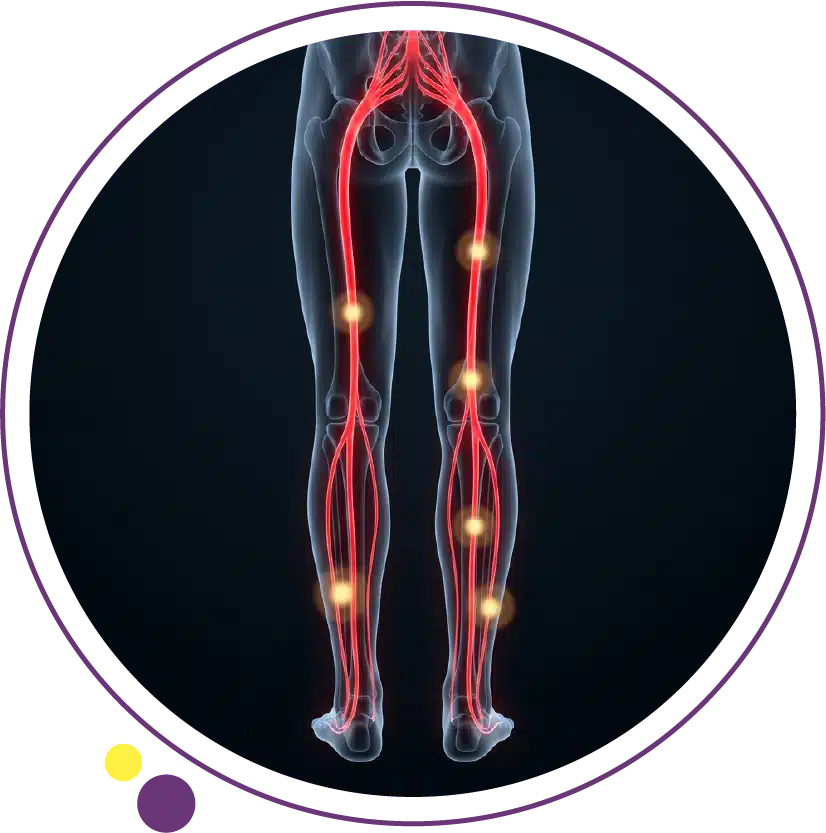

عندما يبدأ المريض بالبحث عن أعراض عرق النسا، فغالباً يكون السبب ألماً يبدأ من أسفل الظهر أو الأرداف ثم ينزل إلى الساق بطريقة غير معتادة. عرق النسا ليس مرضاً مستقلاً، بل هو نمط من الأعراض يحدث غالباً عندما يتهيج أو ينضغط جذر عصبي في أسفل العمود الفقري، فتظهر الأعراض على امتداد العصب الوركي. ولهذا يكون ألم الساق في كثير من الحالات أوضح من ألم الظهر نفسه.

المهم أن هذا الألم ليس دائماً مجرد شد عضلي. فعرق النسا قد يسبب ألماً حارقاً أو طاعناً أو يشبه الصدمة الكهربائية، وقد يصاحبه تنميل أو خدر أو ضعف في الساق أو القدم. كما أنه غالباً يصيب جهة واحدة من الجسم، وقد يزداد مع الحركة أو السعال أو العطاس أو الجلوس الطويل.

أعراض عرق النسا هي أعراض عصبية تنشأ عادة من أسفل الظهر ثم تمتد على مسار العصب الوركي إلى الأرداف وخلف الفخذ وربما إلى بطة الساق والقدم وأصابعها. وقد تشمل الألم والتنميل والوخز والضعف مع كون الأعراض أوضح في الساق من الظهر في كثير من المرضى.

السبب في هذا النمط أن الإشارة العصبية نفسها تصبح مضطربة. لذلك فإن الإحساس لا يكون مثل ألم العضلات العادي. بعض المرضى يصفونه بحرقان، وآخرون بصعقة كهربائية، وآخرون كألم نافذ ينزل على امتداد الرجل. وقد يظهر فجأة أو يبدأ تدريجياً.